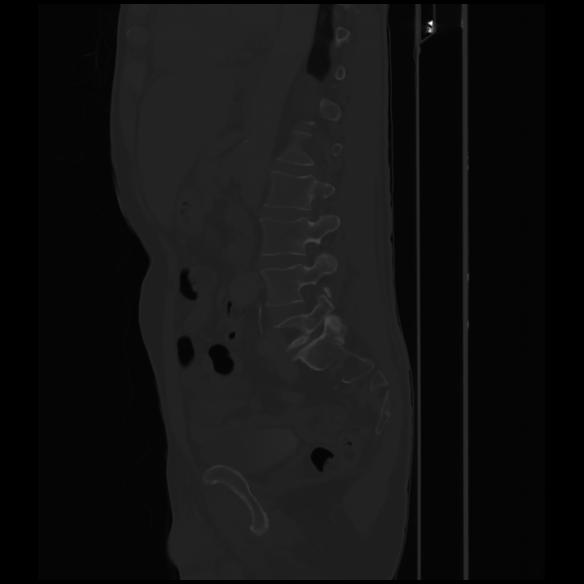

7 CUERPO,CE,Sagittal,3.000,CUERPO,Sagittal,